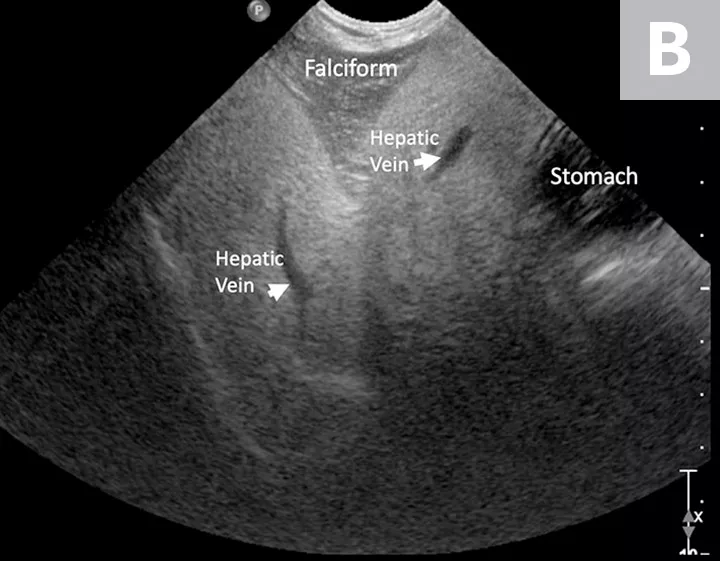

The liver, gallbladder, biliary tract, duodenal papilla, and pancreas should be examined with a high-frequency transducer, and, because these structures are in the cranial abdomen, it is usually best to use a curved-array transducer with a small footprint.

Ultrasonography is useful for estimating hepatic size and evaluating internal architecture (including portal, venous, arterial, and biliary vasculature; echogenicity; and echotexture). Size, wall thickness, and contents of the gallbladder, as well as size of the bile ducts, can also be assessed. Ultrasonography is also helpful for differentiating chronic injury (eg, cirrhosis, end-stage chronic inflammatory disease) from acute liver injury based on the size, shape, and internal architecture of the liver parenchyma.2